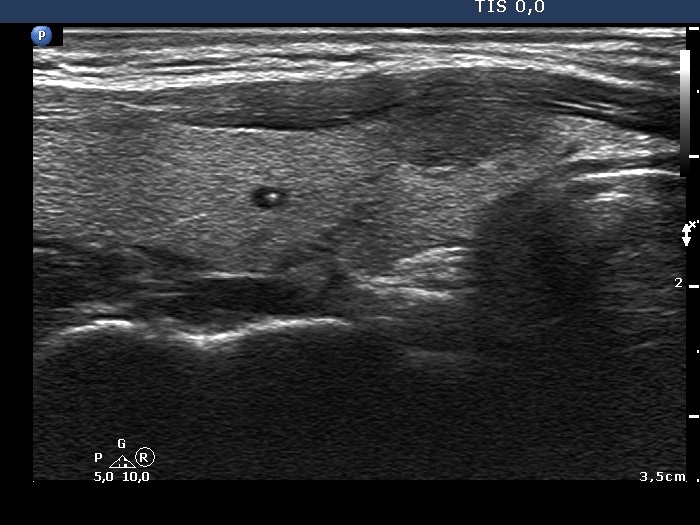

One year after the first examination (ultrasonographic picture 5)

Right lobe, longitudinal scan

Right lobe, longitudinal scan. Note a small cystic area having a bright echogenic figure.